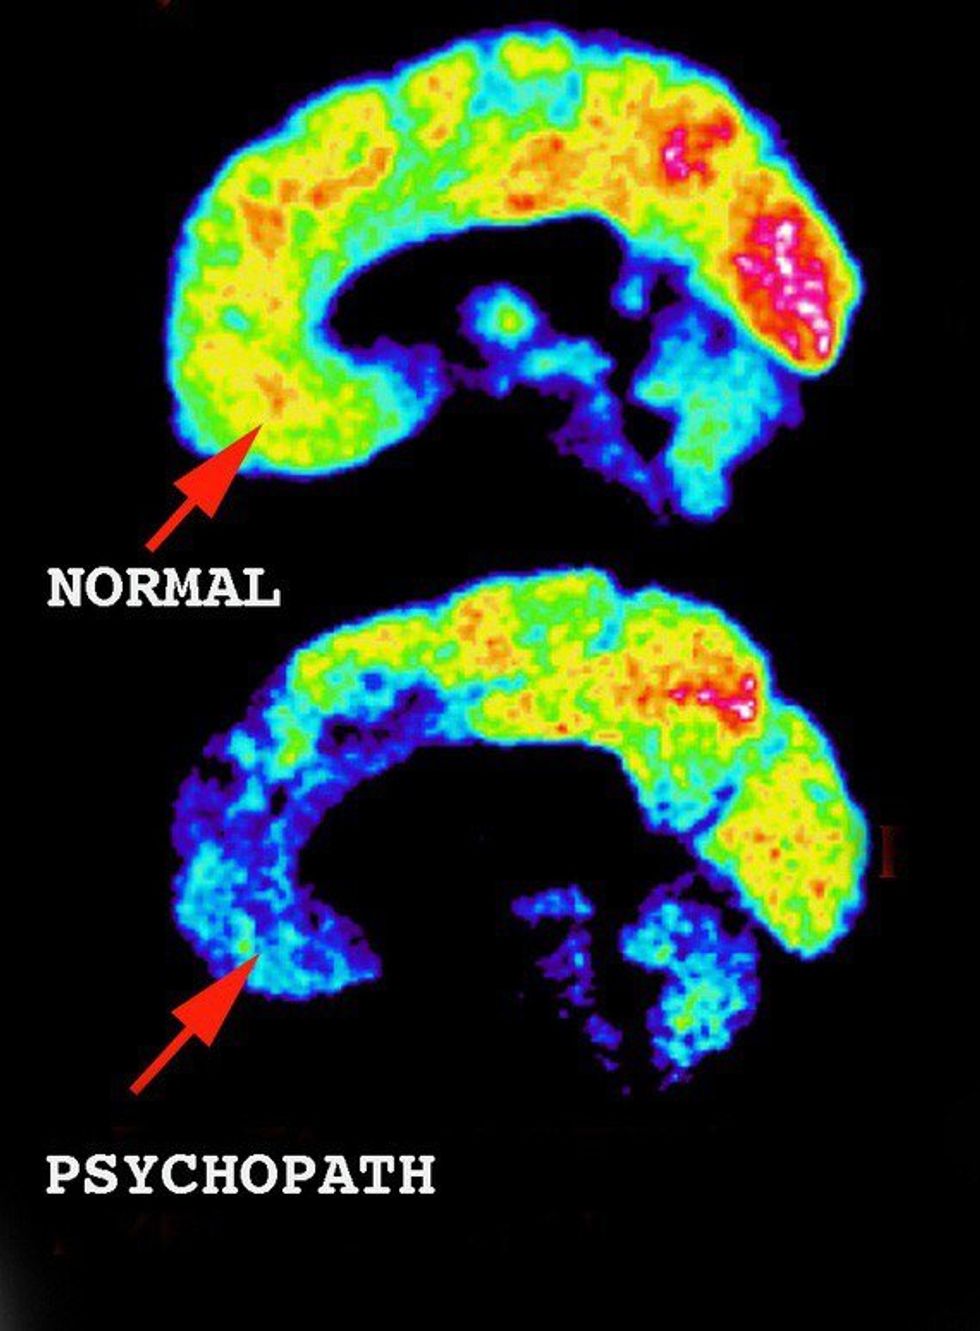

About a quarter way into the movie, we paused it to share our attraction to the human brain. What makes me normal? What makes another person disturbed enough to murder people? Does it have to do with their genetics? Childhood? Is it a case of nature verses nurture? What makes people do the things they do? I am not a psychiatrist or any kind of doctor, but I have done a good bit of research and what I have found is amazing and terrifying all at the same time.

The more common diagnosis of psychopaths comes from the Diagnostic and Statistical Manual of Mental Disorders (DSM). This manual describes psychopathy as an "Antisocial Personality Disorder." Psychopaths are often regarded as those who are morally depraved, where tendencies are linked to genetic traits. The term sociopaths, frequently misused, refers to those who are less dangerous and become sociopaths due to their environment.